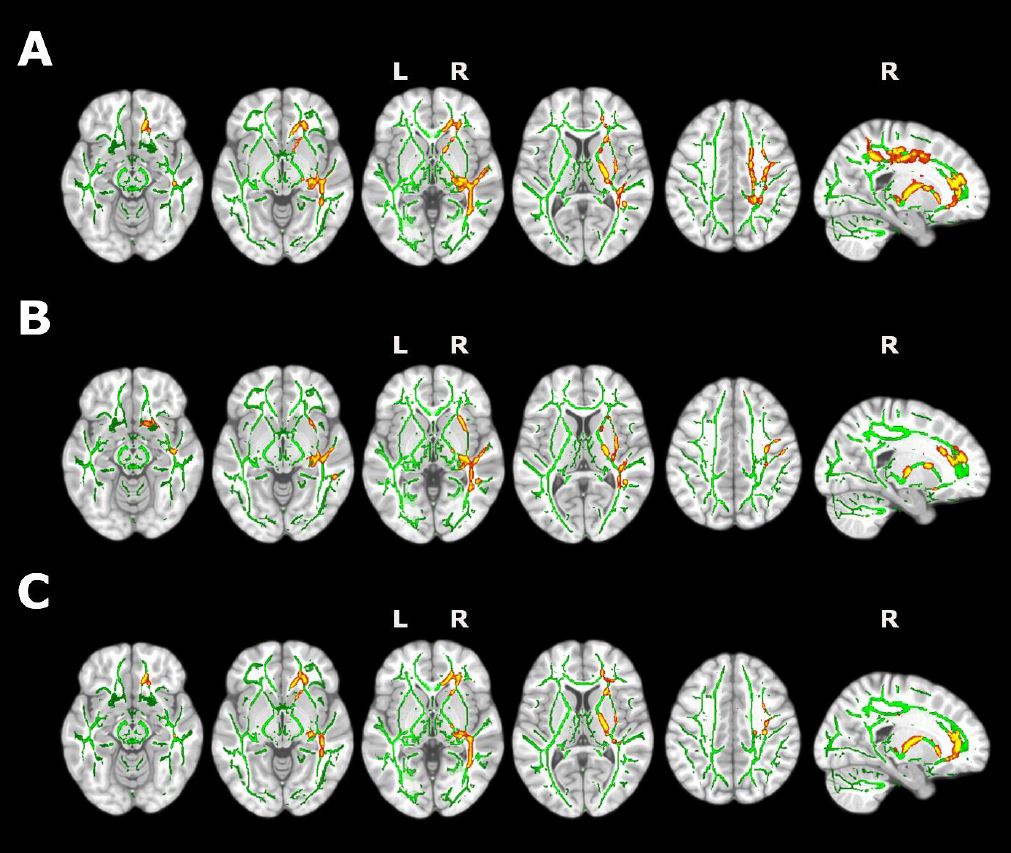

Avanzan en el conocimiento de la arquitectura genética de la corteza cerebral humana